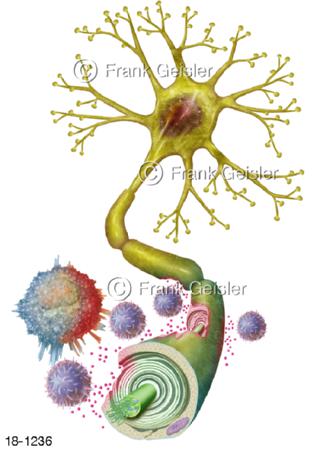

18-1236 Multiple-Sklerose MS, Neuron mit Markscheide